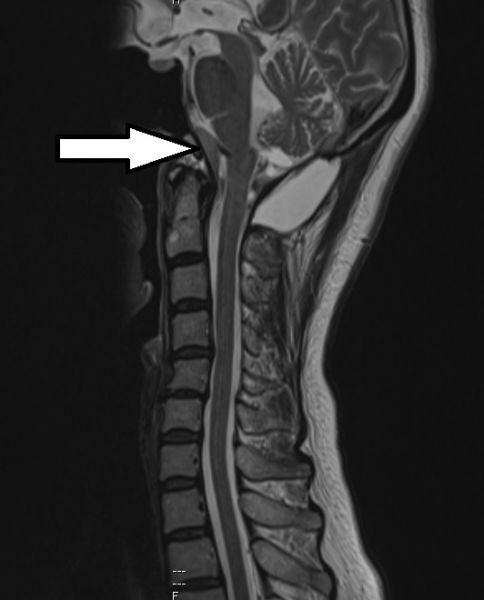

在这之前,法拉已经在另一所私人医院做了颈椎扫描,知道颅底的枕骨大孔处长了一颗脑膜瘤(Foramen magnum tumor with cord compression),压迫神经中枢,导致她目前面对的种种健康状况。

脑膜瘤属良性肿瘤,但法拉脖子里的这颗脑膜瘤生长的位置十分刁钻,令手术变得非常棘手。肿瘤长在颅底的枕骨大孔内,除了神经管,旁边还有给后脑和脑干供血的主要血管,万一手术刀不慎伤及神经线会造成瘫痪,伤及血管则可会引起中风。手术刀要如何绕过神经线和血管,直达肿瘤,将肿瘤安全切除,是主刀医生的一大挑战。